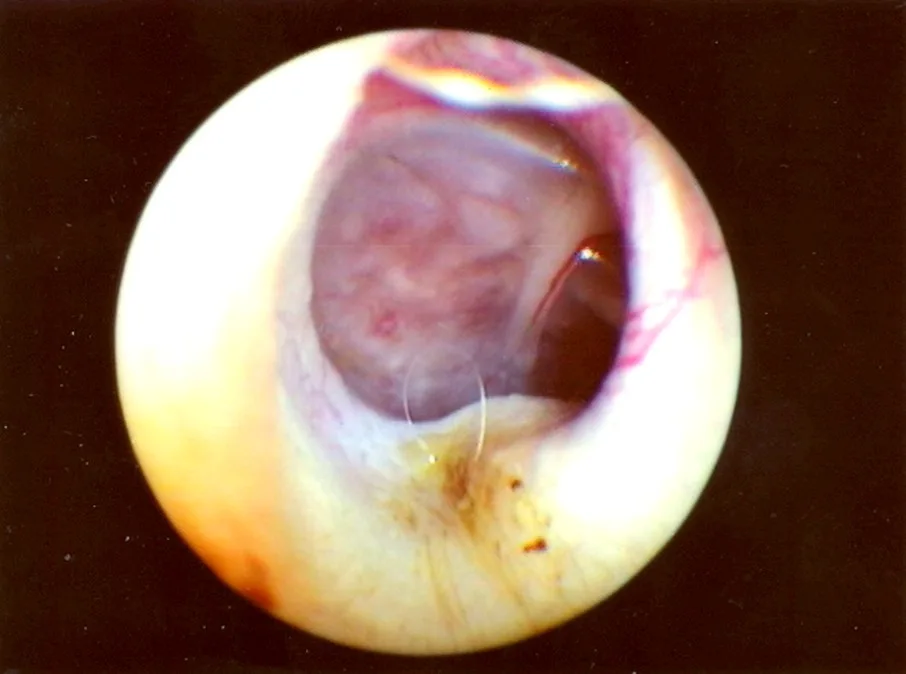

Bulging eardrum identified on otic examination (Figure 1)

FIGURE 1 Middle ear exudates fill tympanic bulla, putting painful pressure on the eardrum and causing it to bulge outward.